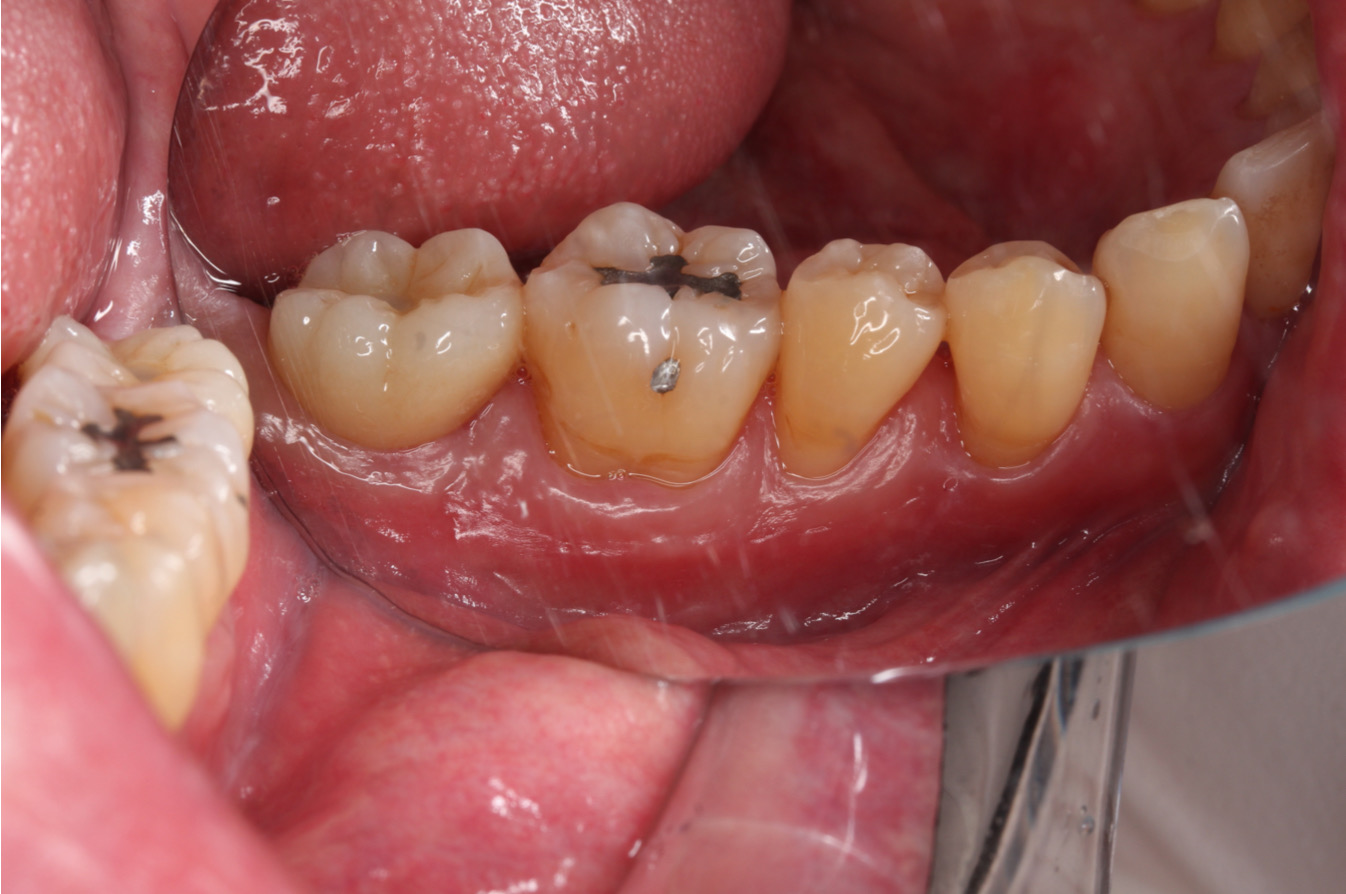

植牙的角化牙齦移植術|提升植牙成功率與美觀性,除了缺牙區,牙肉也要重建!

【治療醫師:林農翔 醫師】   植牙的角化牙齦移植術 植牙的角化牙齦移植術是一種在植牙手術中常見的程序,旨在改善患者缺牙區域的牙齦狀態,提高植牙的成功 …